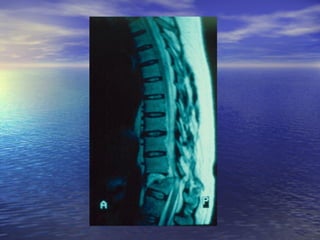

ΑΑππεειικκοοννιισσττιικκόόςς ΈΈλλεεγγχχοοςς

MM..RR..II..

ΕΕξξέέτταασσηη εεππιιλλοογγήήςς σσεε ππεερρίίππττωωσσηη

ννεευυρροολλοογγιικκήήςς σσηημμεειιοολλοογγίίααςς

ΑΑππεειικκοοννιισσττιικκόόςς ΈΈλλεεγγχχοοςς MM..RR..II.. ΕΕξξέέτταασσηη εεππιιλλοογγήήςς σσεε ππεερρίίππττωωσσηη ννεευυρροολλοογγιικκήήςς σσηημμεειιοολλοογγίίααςς